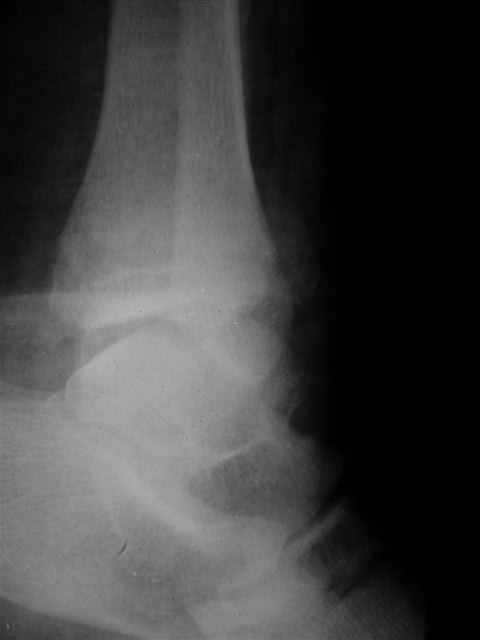

> Если Вас не затруднит, пришлите, пожалуйста, рентгенограммы. Я

> интересуюсь тактикой лечения повреждений голеностопного сустава.

> Хочется посмотреть, как лечат коллеги.

Ничего сверхъестественного, но если есть интерес, то в понедельник пересниму Рг-граммы и отправлю.

Уважаемый Иван,

Я предупреждал, что ничего сверхъестественного. Каюсь, что одна из спиц прошла несколько дальше, чем нужно было, но главное - перелом стабилизирован и больной работает суставом в полном объёме, несмотря на представленную раннее травму коленного сустава.